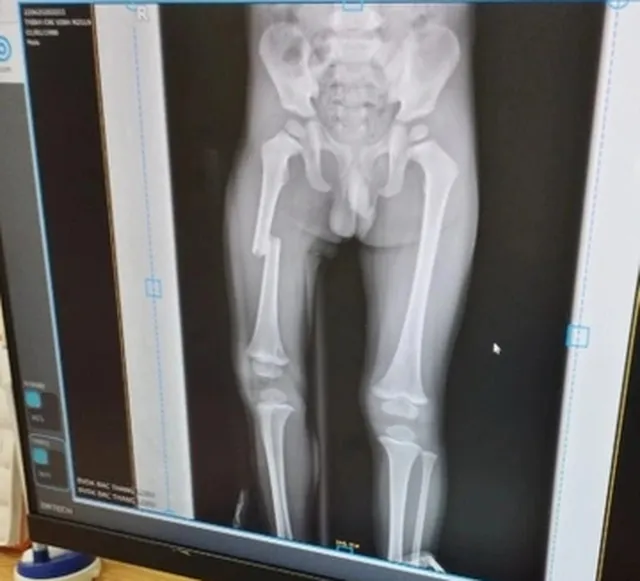

Lập hồ sơ xử lý người phụ nữ đạp gãy chân con trai ảnh 2 Phim chụp Xquang cho thấy cháu bé bị gãy xương đùi

Cụ thể, vụ việc được xác định xảy ra tại một nhà dân ở xã Quý Sơn, huyện Lục Ngạn, tỉnh Bắc Giang từ tháng 6-2022. Cháu trai trong clip đã bị gãy xương đùi nhưng đến thời điểm hiện tại đã khỏi và hoàn toàn có thể đi lại bình thường.